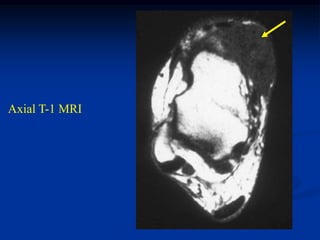

Sagittal T-1 MRI

14 year male with desmoid tumor hand 2 years

Case #253.1 Sagittal T-1 MRI 14 year male with desmoid tumor hand 2 years